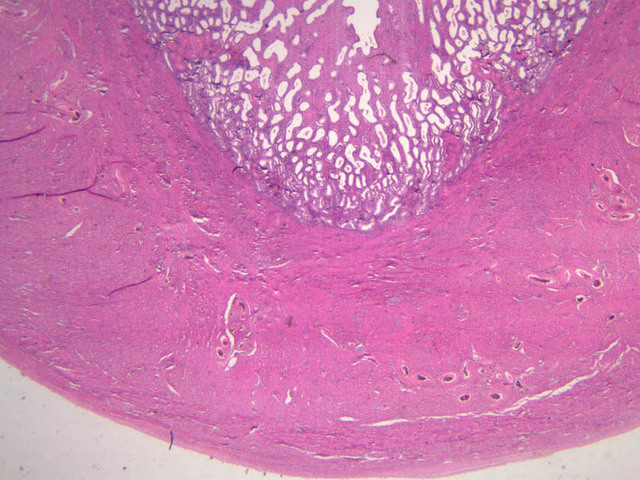

Corpus Luteum

After rupture of the Graafian follicle, the walls collapse and become folded. Thus, strands of tissue from the theca interna penetrate, to some extent, the mass of granulosa cells. Bleeding from the theca interna may form a blood clot in the antrum. The majority of the cells of the corpus luteum are derived from the granulosa cells. Both the granulosa cells and the cells of the theca interna enlarge and accumulate lipid, thus becoming lutein cells. There are two types of lutein cells - granulosa lutein cells that have a large, vesicular nucleus and vacuolate cytoplasm, and theca lutein cells that are distinguished by smaller darker nuclei. Corpus Luteum (slide B-54, human ovary, H&E [1x-labeled, 2.5x, 10x, 20x, 40x-labeled] [1x-labeled, 1x, 2.5x] [1x, 1x, 1x] 1x, 2.5x, 10x]; B-95, H&E [2.5x])

Corpus Albicans

The corpus luteum persists for 12 to 14 days. If fertilized ovum does not implant, the corpus luteum degenerates, leaving a scar which is referred to as the corpus albicans. This will also disappear eventually. Some of the B-54 slides in our collection have corpus albicans – try to identify a corpus albicans on your slide or consult with your neighbors. Corpus Albicans (some B-54 [1x-labeled] [2.5x] [1x-labeled, 2.5x, 10x])